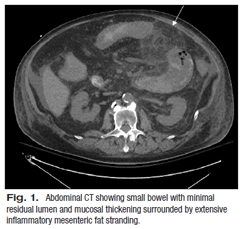

Fig 1

His multiple comorbidities made him a poor surgical candidate, and conservative management with the addition of metronidazole was initiated on hospital day four. Although he showed initial improvement, his abdominal symptoms progressively worsened. He had a heme-positive bowel movement on hospital day 14 with stool culture negative for Clostridium difficile and Norovirus; planned additional studies were not performed due to insufficient material. Repeat abdominal CT on hospital day 15 showed progression of the abdominal process (Fig. 1). The next day he had blood per NG tube, left upper quadrant ecchymosis, increased abdominal distension, and an underlying palpable mass. He continued to decompensate until hospital day 18 when he died after unsuccessful resuscitative efforts for bradycardia, acute hypotension, and acidosis.